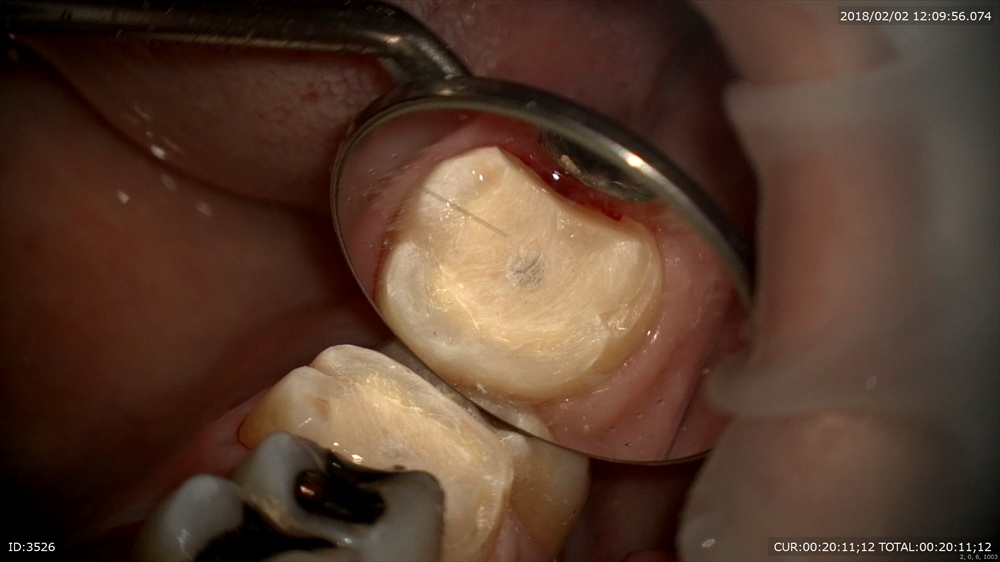

次は精密根管治療の後の処置。MTAで根管充填し細菌感染を防ぐ為即日ファイバーコアを築造。

術前(精密根管治療)と本日

ここまで根管治療が始まってから3回。1回の時間をしっかりとることで数回でかめるようになりました。この方は他院での根管治療が治らず去年来院。悩まれていましたが症状が消え笑顔が戻りました。